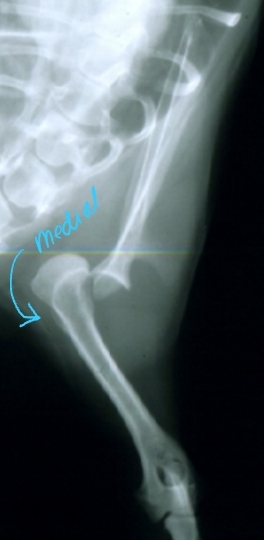

Hip Luxation Pathophysiology

Et: Results from failure or tear of Joint capsule or Round ligament

Most common joint luxation in dogs

Types:

Craniodorsal (#1): hit-by-car or blunt trauma

Caudoventral: fall with abduction

Hip Luxation Diagnosis

Cs: Crepitus, pain, shortened limb length(craniodorsal), pelvic asymmetry

Palpate: Iliac crest(wing), Greater trochanter of femur, and Ischiatic tuberosity form a straight line

Normal = shallow triangle

Thumb test: Place thumb in ischiatic notch and externally rotate limb

Normal = Thumb should be pushed out of notch

Radiographs: lateral & VD